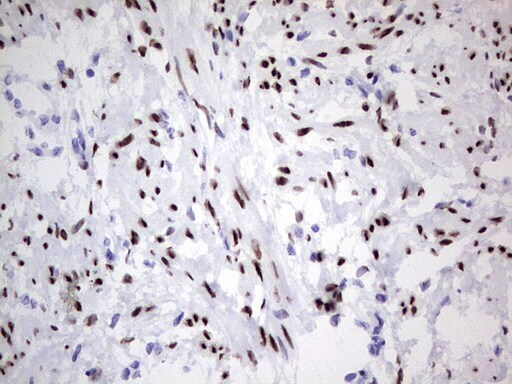

- Submitted by

- Invitrogen Antibodies (provider)

- Main image

- Experimental details

- Immunohistochemical staining of paraffin-embedded Adenocarcinoma of Human endometrium tissue using anti-PGR mouse monoclonal antibody. (Heat-induced epitope retrieval by 1 mM EDTA in 10mM Tris, pH8.5, 120°C for 3min, TA805108)